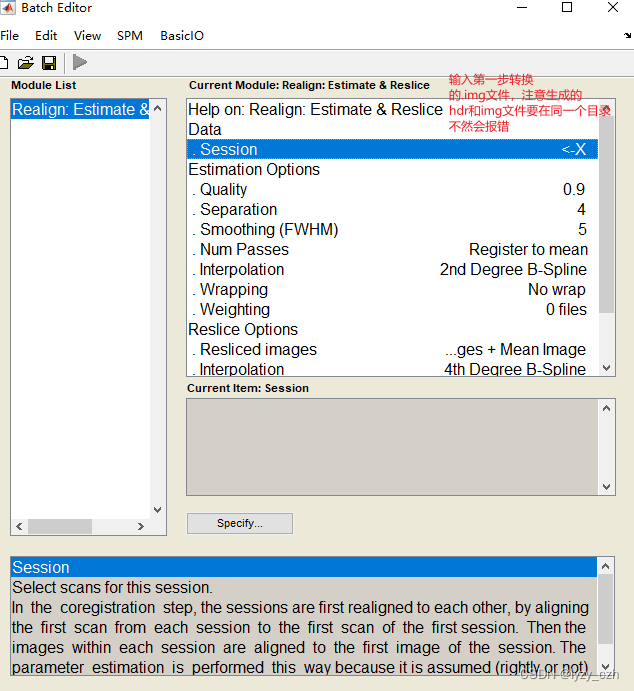

2) Realign,只需要编辑Session,其他参数不用改,编辑好后点击左上角绿色三角形按钮: